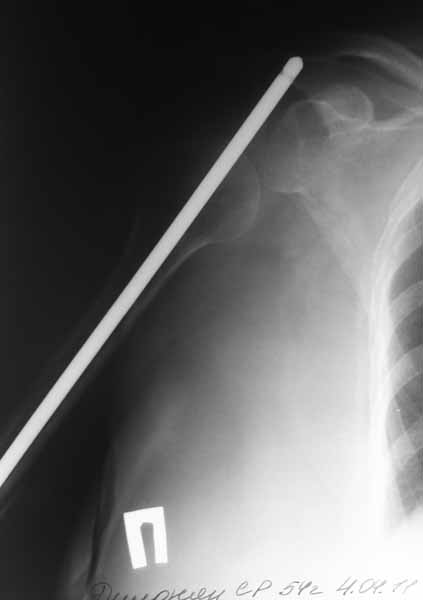

Доброго времени суток уважаемые коллеги.Представляю вашему вниманию пациентку 54 лет.Из

анамнеза: травма в сентябре 2010 года в результате падения. В ЦРБ по м/ж выполнена открытая

репозиция, синтез штифтом Кюнчера и проволочным серкляжами. Рана заживала первично.

Такая исходная длинна штифта разъяснена пациентке как "непринципиальный" момент в общем

процессе лечения. Гипсовая иммобилизация 2 месяца. По снятию гипсовой повязки пациентка

отметила резкое снижение объема движений в плечевом суставе. Активное длительное ЛФК без

эффекта.

Спустя 6 месяцев после операции пациентка госпитализирована к нам в клинику. После

выполнения контрольных рентгенограмм помимо атрофичного ложного сустава н\3 плечевой

кости был диагностирован нижний вывих головки плечевой кости.

Первым этапом выполнено удаление металлоконструкции и БИОС плечевой кости с костной аутопластикой плечевой кости.